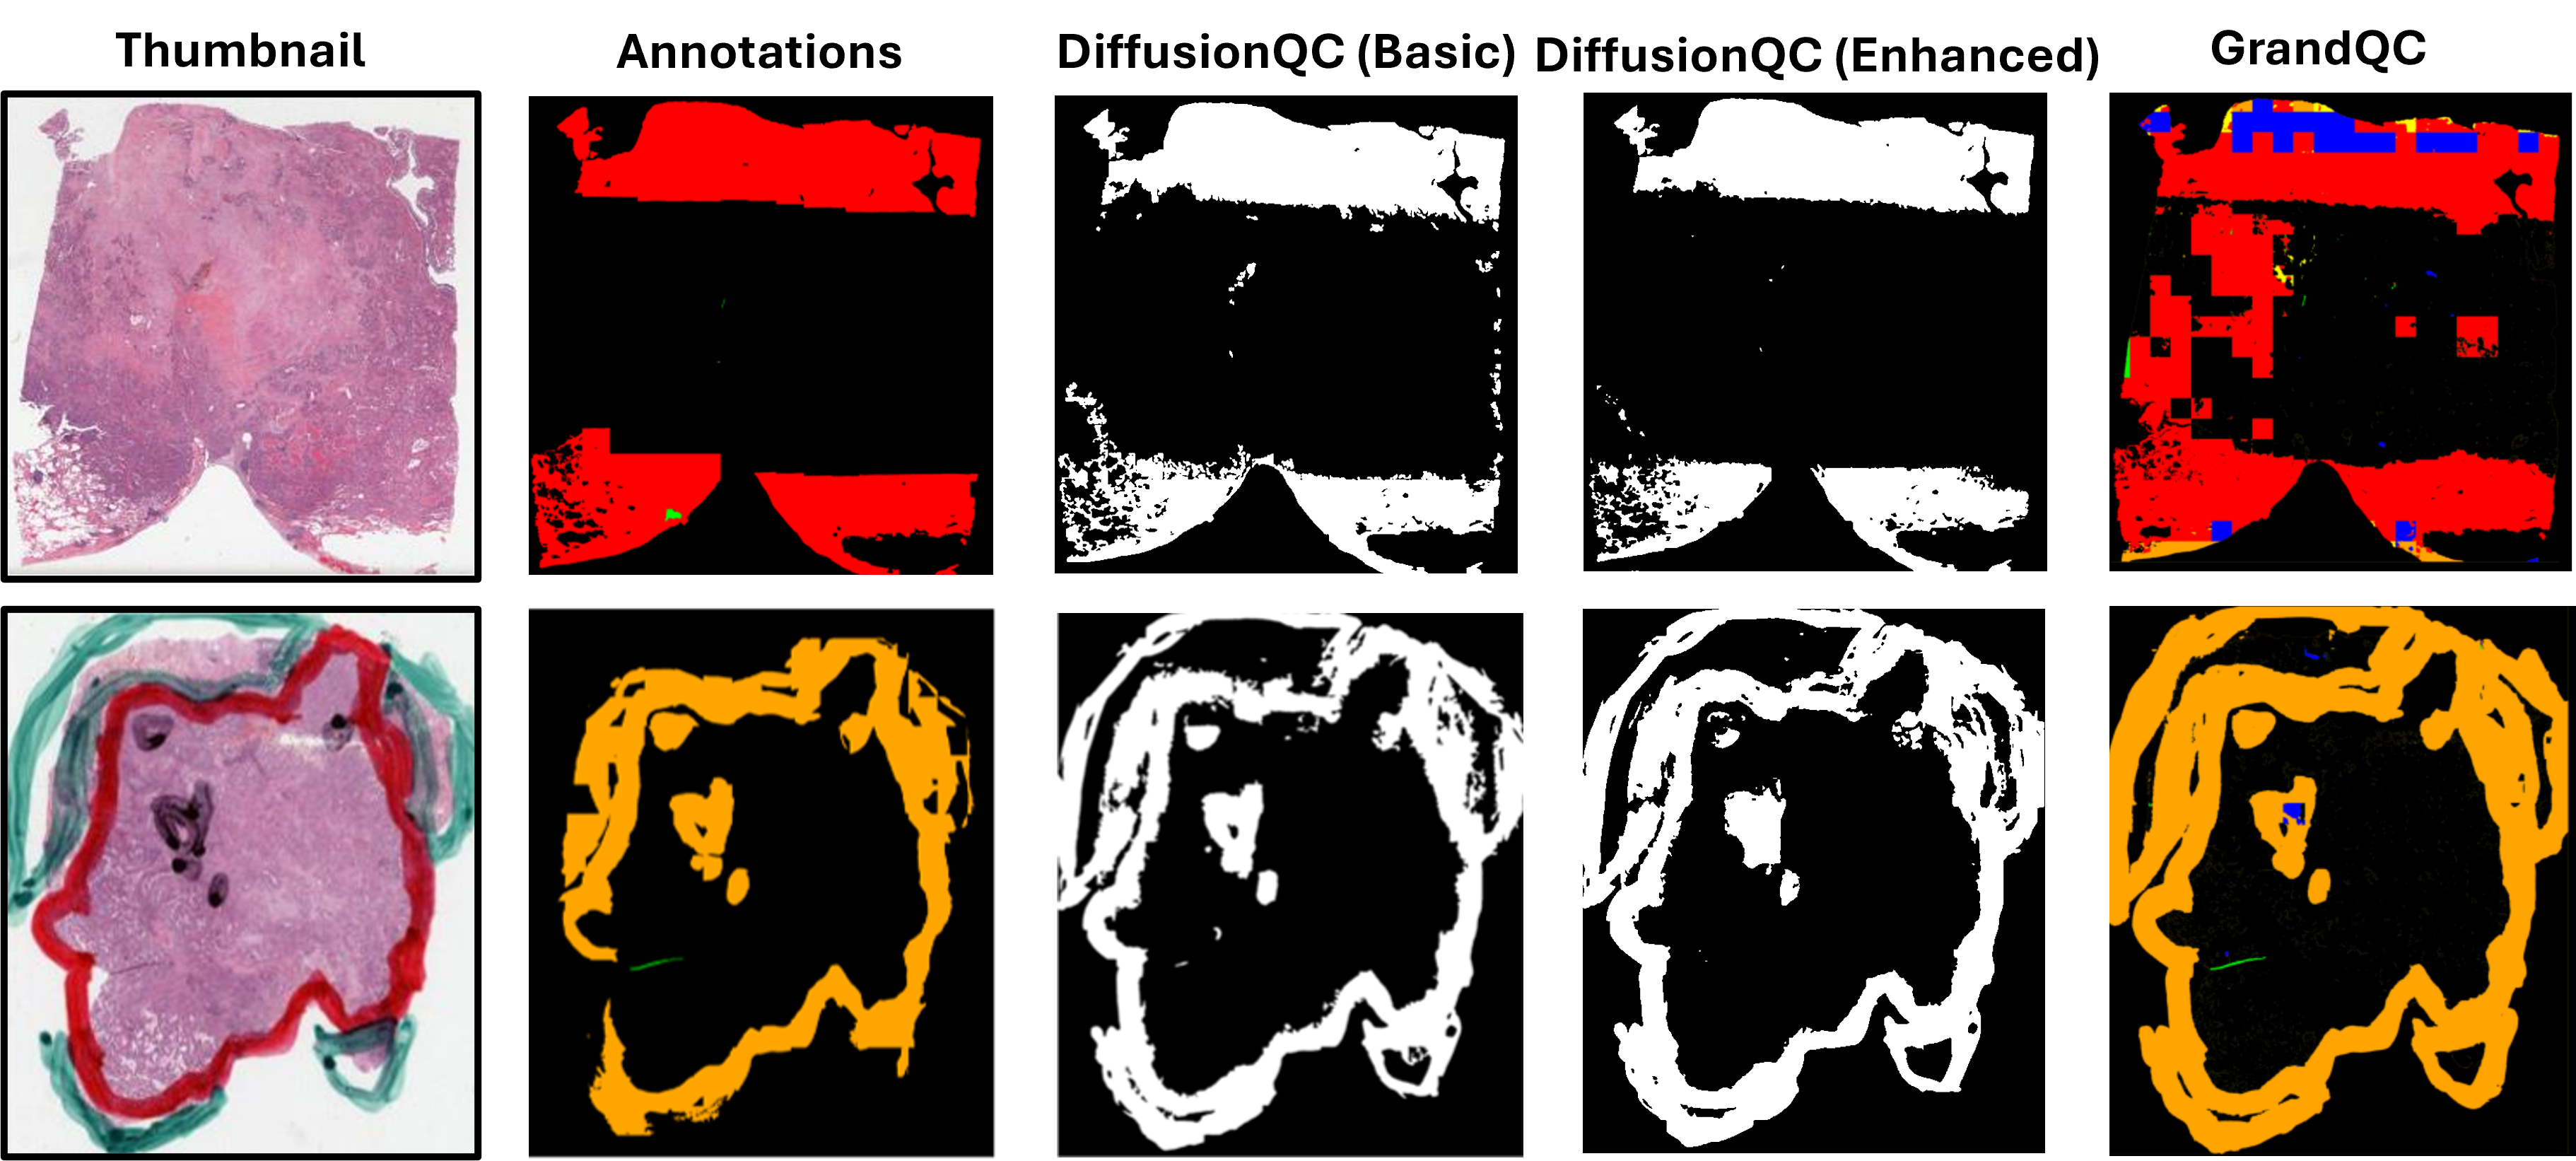

We evaluate the performance on 24 held-out WSIs and consider manual annotations as ground truth. For each artifact type, detection sensitivity is calculated; additionally, we aggregate all artifact categories into a binary classification task and report the sensitivity, precision, and F1 scores. We compare with the state-of-the-art method, GrandQC. As summarized in Table 1, the basic version of DiffusionQC already achieves comparable performance to GrandQC, while the enhanced version outperforms it in most metrics. Importantly, DiffusionQC uses significantly fewer resources: GrandQC was trained on 420 WSIs with pixelwise annotations for artifacts, whereas ours uses only 14 WSIs with coarse patch-level labels. Several representative examples are shown in Figure 3. Furthermore, we evaluate cross-stain generalization by directly applying the enhanced model solely trained on H&E slides to an internal set of IHC-stained images. Although quantitative evaluation is not feasible due to the lack of ground truth annotations, we provide qualitative visualization in Figure 4. The detection results of GrandQC and DiffusionQC are displayed side by side, with representative zoom-in patches shown below. DiffusionQC clearly demonstrates stronger detection capacity and visual consistency. Various artifacts, including air drop (blue box), OOF (red), dark spot (purple), folding (orange), and foreign objects (cyan), are successfully detected even without finetuning on IHC images. In contrast, GrandQC shows limited generalization, missing most key artifacts and falsely labeling clean regions as artifacts (yellow box).